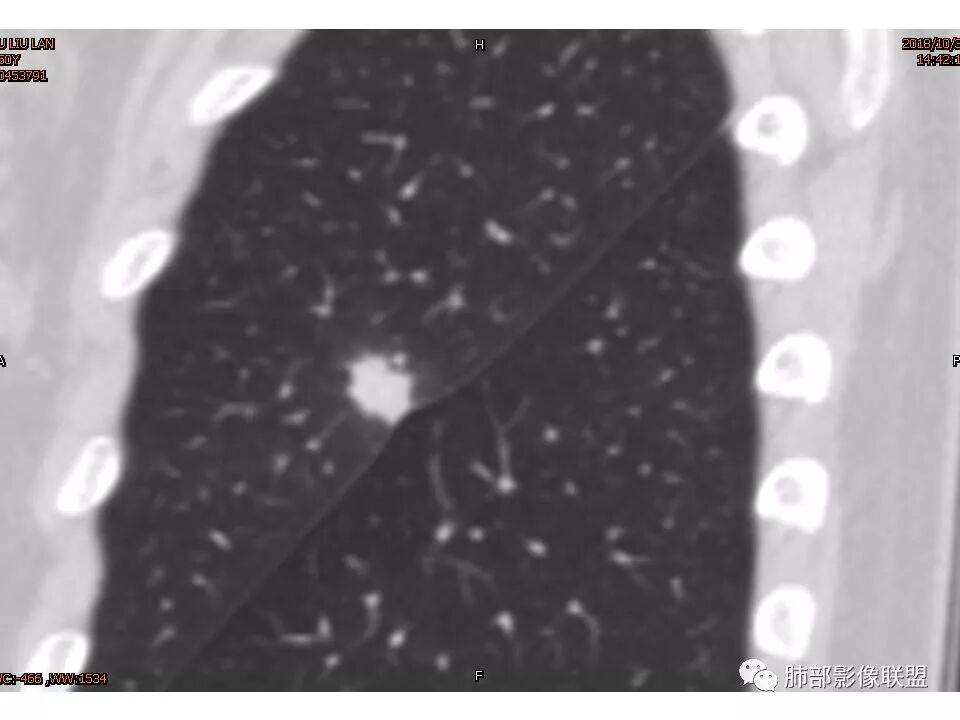

鉴别:腺癌 牵拉斜裂,有动静脉相连,

左肺上叶结节,部分边缘膨隆,边缘毛刺,斜裂牵拉,增强中度强化,血管穿行,血管略增粗。考虑肺癌,腺癌可能性大,鉴别肉芽肿性炎

左肺上叶结节影,病灶周围呈磨玻璃样改变边缘见毛刺、分叶及胸膜牵拉,增强扫描病灶明显强化,病灶未跨叶间裂,考虑炎性病变,待除外小腺癌。

考虑恶性可能性大,毛刺分叶,局部膨隆。收缩明显,牵拉叶间裂

考虑恶性可能性大,毛刺分叶,局部膨隆,牵拉叶间裂收缩明显

1.胸膜下略不规则实性密度结节影,孤立,缺乏典型深分叶,可见淡薄边界模糊磨玻璃晕,可见相对细长软毛刺。

2.如南边老师分析,病灶缺乏边缘膨隆优势,甚至部分平直内收。

3.病灶收缩力不强,整体强化程度不显著。

4.综上,病灶更符合炎性,如隐球菌感染等,而不大符合肺腺癌。具体到机化性肺炎略有些出乎预料。